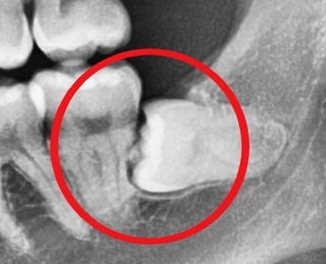

사랑니가 나오는 방향, 위치, 각도가 올바르지 못해 통증과 붓기를 유발하여 불편함 초래

일상생활의 불편함사랑니가 나오는 방향, 위치, 각도가 올바르지 못해 통증과 붓기를 유발하여 불편함 초래

어금니 뒤쪽의 사랑니는 치아관리를 못해 충치/염증/구취를 유발 가능

구강관리의 어려움어금니 뒤쪽의 사랑니는 치아관리를 못해 충치/염증/구취를 유발 가능

깨끗하게 관리를 하지 못하는 사랑니주변 치아까지 문제가 될 수 있음

주변치아의 영향 등깨끗하게 관리를 하지 못하는 사랑니주변 치아까지 문제가 될 수 있음

사랑니가 나오는 방향, 위치, 각도가 올바르지

못해 통증과 붓기를 유발하여 불편함 초래